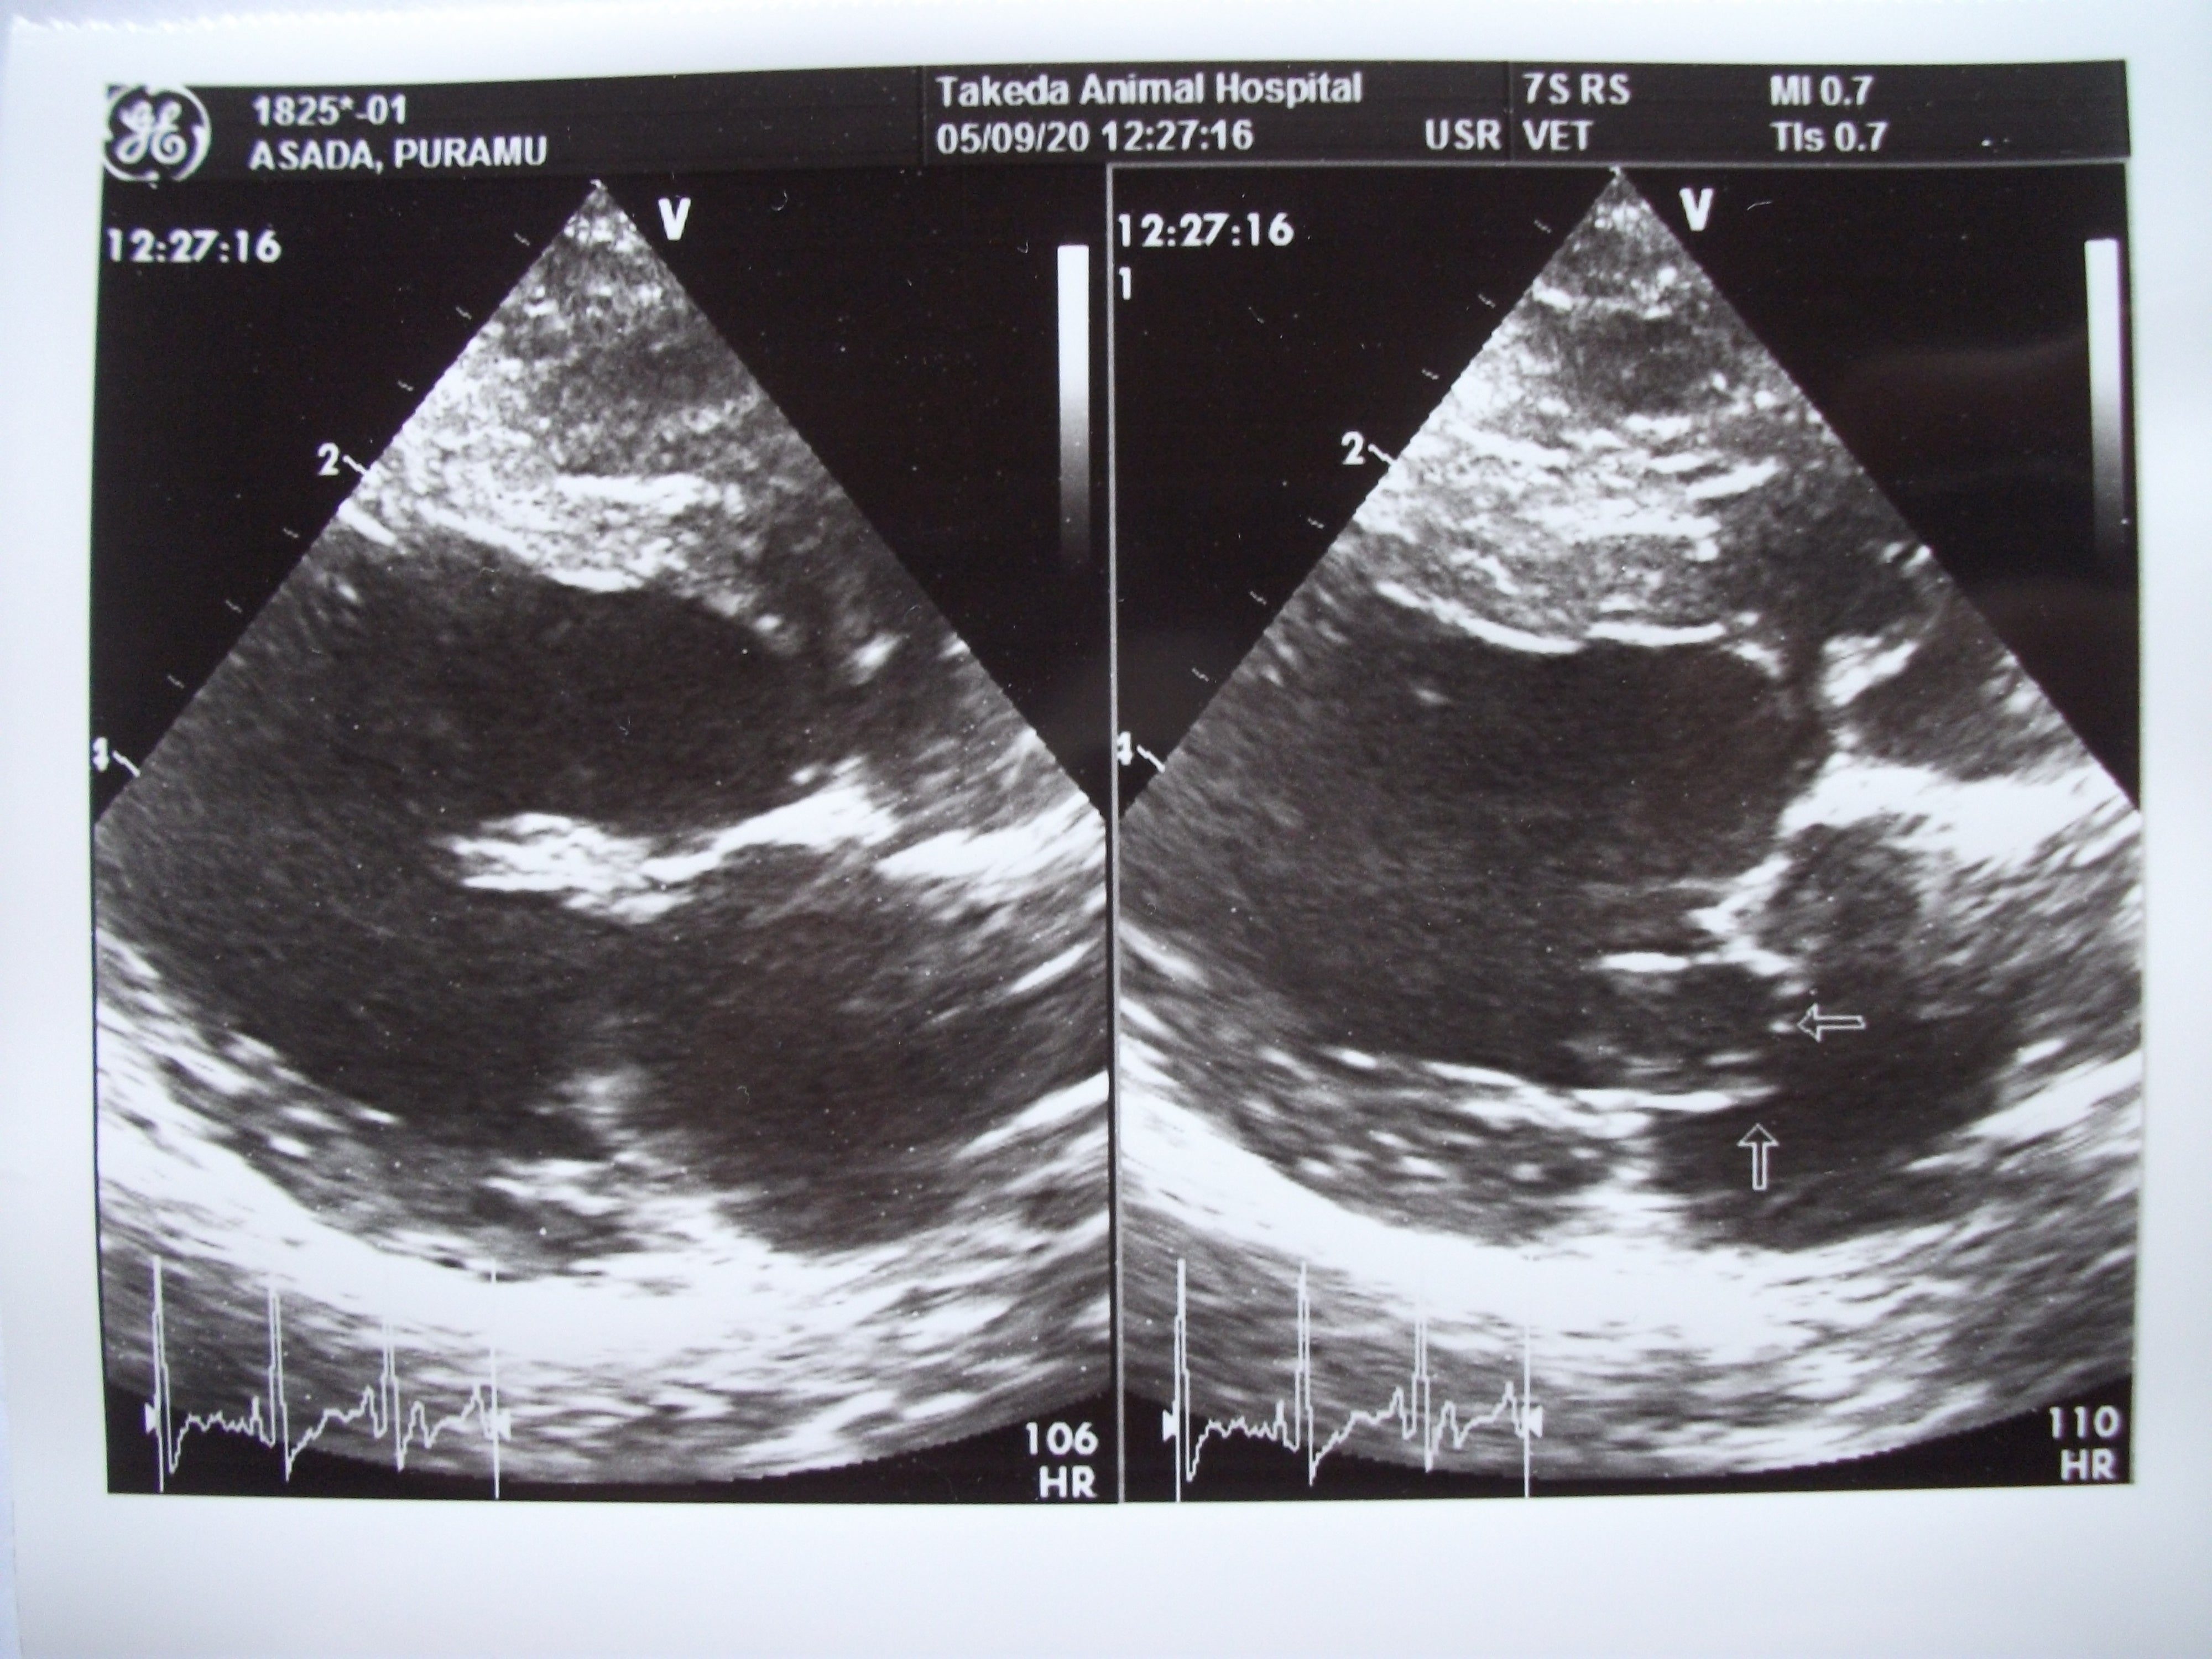

2020年5月9日の診断

右側の写真の矢印部分、くの字に折れ曲がっていて

この隙間から血が逆流します。

そんなプラムが昨年定期健診の際、心臓に雑音があるとお医者様に言われ、心臓病の僧帽弁閉鎖不全症 と診断されました。

僧帽弁とは、心臓の左心房と左心室の間に位置する2枚の薄い弁で健康な状態なら心臓が収縮する時に閉鎖し、左心房への逆流を防いでいます。しかし、この僧帽弁閉鎖不全症という病気はこの弁が完全に閉鎖できず、心臓が収縮する際に全身へ拍出されるべき血液の一部が弁のすき間から左心房へ逆流する状態になる病気です。その結果、左心房の圧が上昇し、肺のうっ血が起こります。この状態が長く続くと、心不全を起こし、肺水腫(肺に水がたまる)などの呼吸困難や、左心房が大きくなる事により咳(のどに何か詰まったようなしぐさ)をします。また、左心房への血液の逆流により、左心房の壁が障害され、そこから心臓の外へ血液が漏れて、急死する事もあります。

前回の定期健診でこの逆流の量が多くなってきているとお医者様に言われました。心臓の大きさも前回より膨らんできていました。